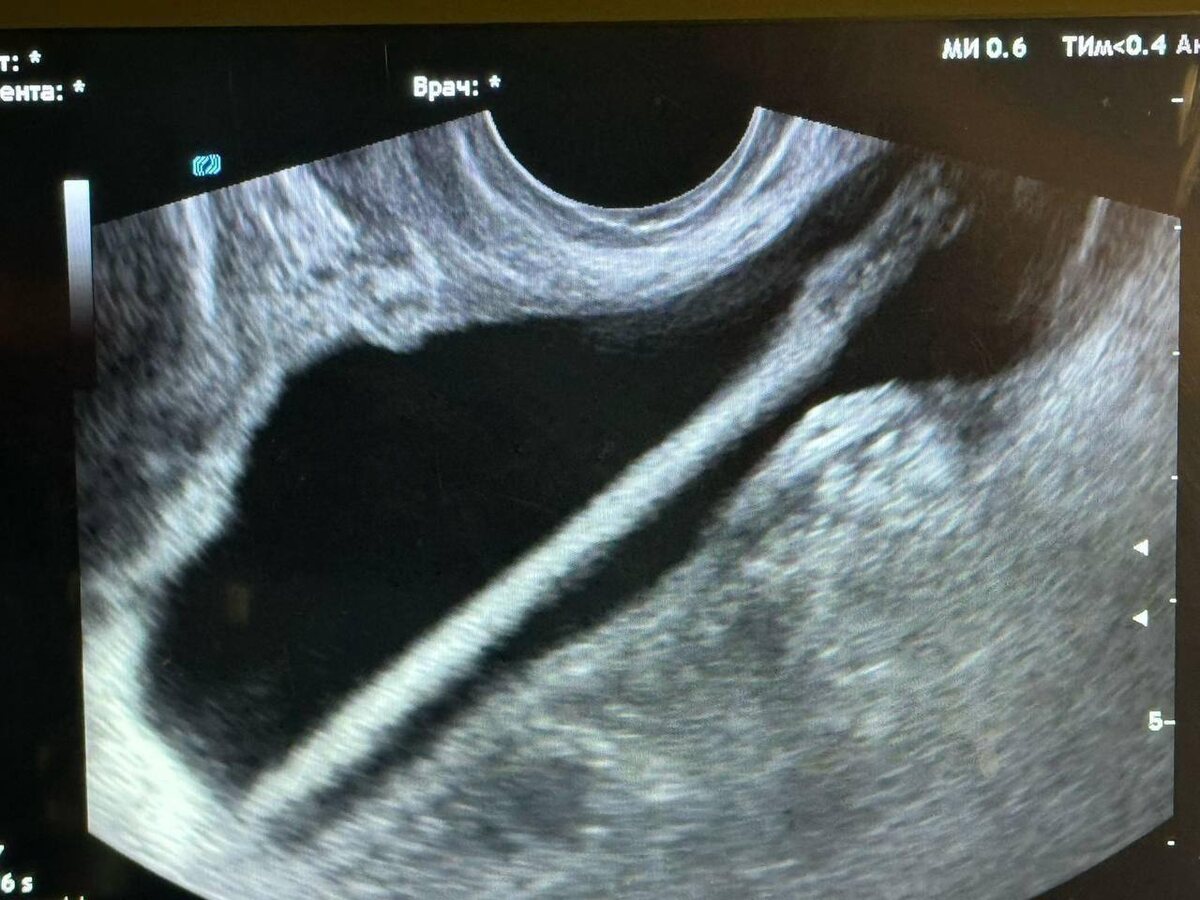

Красногорск, история на грани фантастики. Врачи местной больницы столкнулись с необычным случаем: 46-летняя пациентка самостоятельно ввела косметический карандаш в мочевой пузырь. Причины такого поступка остались загадкой. 🤔

Медики оперативно провели процедуру извлечения инородного тела. Операция прошла успешно, но врачи настоятельно рекомендовали женщине избегать подобных экспериментов в будущем. 💉